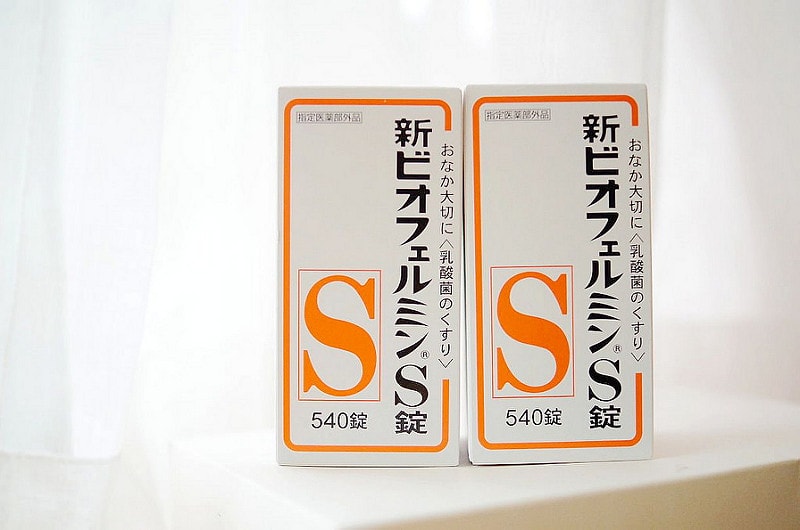

新表飛鳴錠,好像是吃整腸健胃

也有細粉類型,聽說很多媽媽是買來給小孩吃的

這也不是要買來自己吃就一罐給逼媽一罐給南投家裡